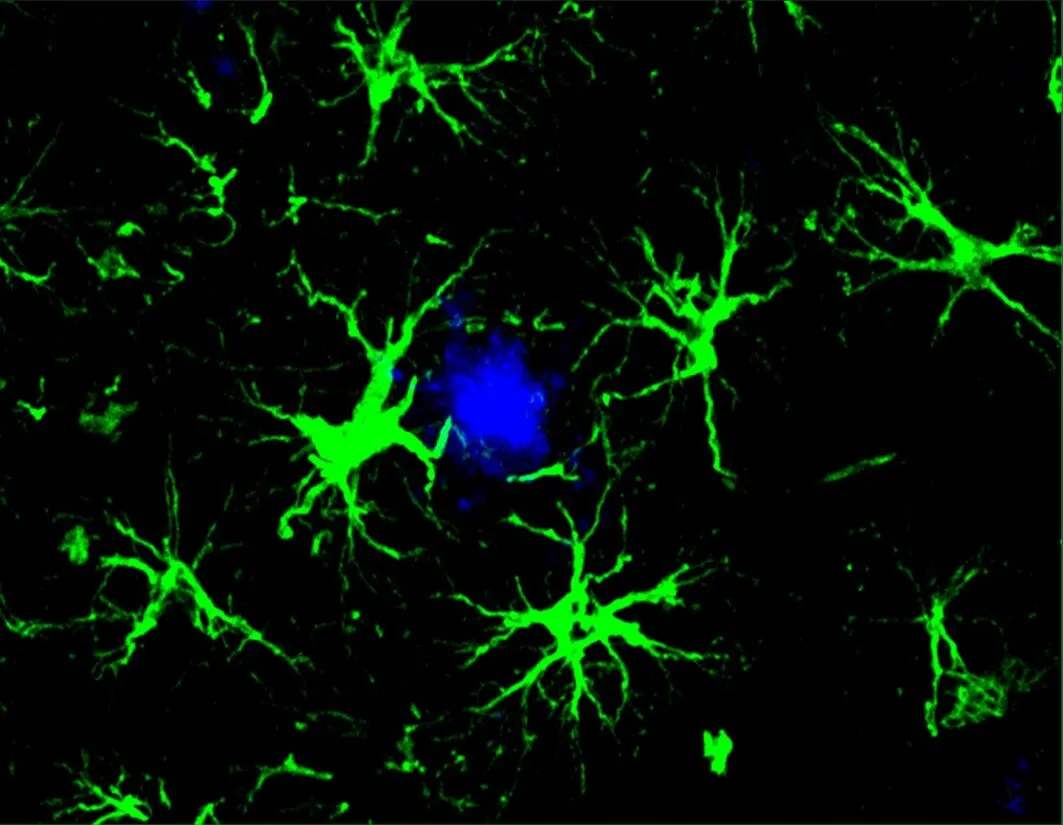

CAR-A疗法(绿色)成功地降低了小鼠大脑中有害的β-淀粉样蛋白斑块(蓝色部分)的数量(来源:Yun Chen,WashU Medicine)

分析结果显示,在第一组更年轻的小鼠中,CAR-A疗法能够阻止β-淀粉样蛋白斑块的形成。在接近6个月大时(此时未经治疗的小鼠的大脑通常已经充满了有害的斑块),接受治疗的小鼠大脑中无斑块形成。与此同时,对于治疗时大脑中已布满斑块的小鼠,接受CAR-A治疗后相较对照组(注射了未携带CAR基因的“空病毒”)β-淀粉样蛋白斑块减少了 50%。